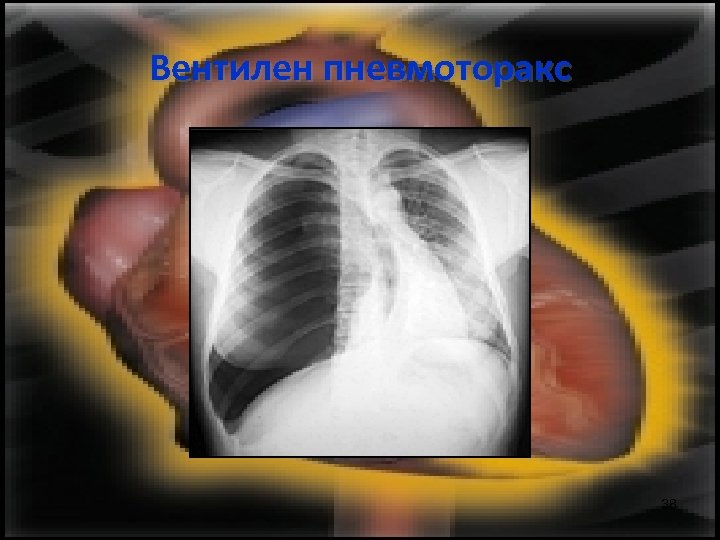

Вентилен пневмоторакс Основното в патогенезата му е, че поради изместването на медиастинума се прегъват съдовете, които постъпват в сърцето и навлизането на кръв в сърцето е преустановено. 35

Вентилен пневмоторакс 37

Вентилен пневмоторакс 38